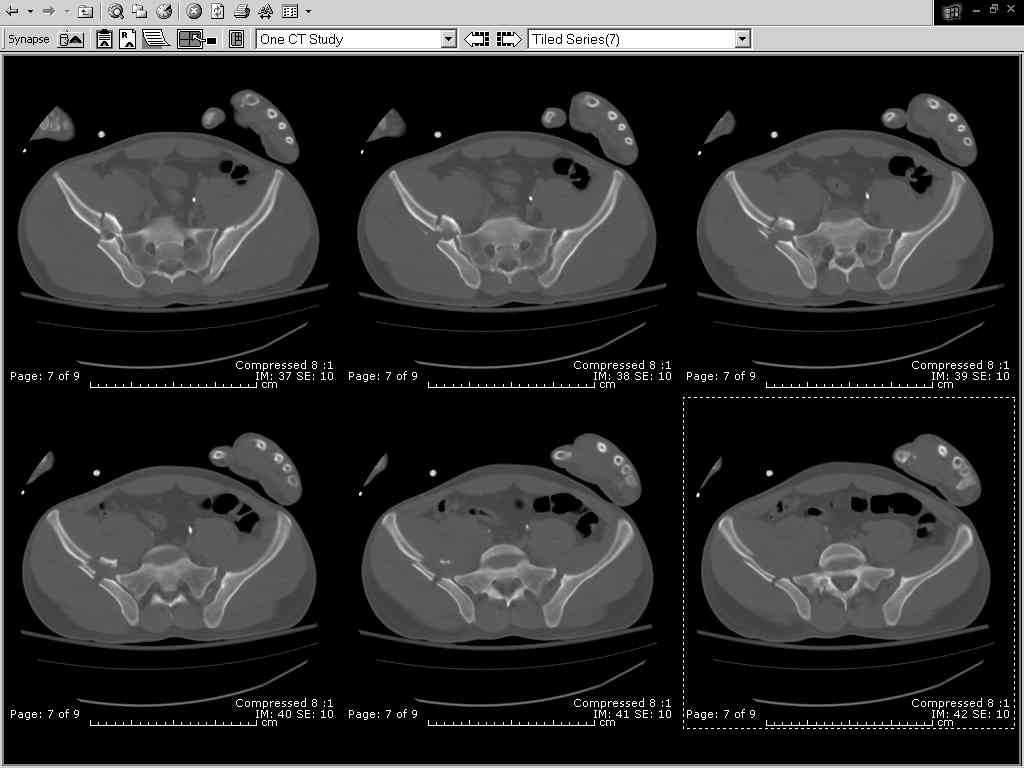

Thanks Adam - I agree it's not a pure APC (is there really such thing as a pure force vector strictly in the x,y or z plane?). I stand corrected. Maybe a hybrid APC (ext rot of L hemipelvis, symphysis disruption, ext rot of R anterior innominate) plus vertical shear as well with 3 or-so cm of cephalad migration of the R ilium. Maybe just "C-type".....

It almost looks to me like an extra-articular both column fx, in addition to the pelvic component. It has the typical triangular fragment and the OO view has a hint of the spur. You may be able to get it all with plates. I would consider fixing the crest first, then a long plate for both symph and iliac portion. SI may close with reduction of symphisis. Looks like the inferior portions are intact. I like your plan as well. You will probably solicit lots of opinion. Good luck. Look forward to post op view.